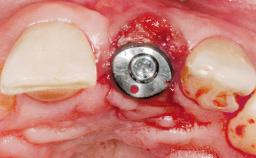

Immediate Flapless Placement of an Implant in a Maxillary Right Lateral Incisor Site

This 43-year-old male patient, a non-smoker, came to our practice because of a fracture of tooth 12 caused by a bicycle accident. Due to the combined para- and infrabony crown and root fracture, tooth extraction, and subsequent implant placement were suggested to the patient as the therapy of choice. The patient had high esthetic expectations with regard to the treatment outcome and asked for an immediate fixed provisional restoration. His individual esthetic risk profile summed up to a medium esthetic risk.

Type of Implants Two-Piece

Placement Protocol Immediate implant placement

Tooth Site Maxillary incisor or canine

Socket Morphology Single-root socket

Socket Integrity Sufficient, with intact bone walls

Bone Volume Sufficient, with intact walls